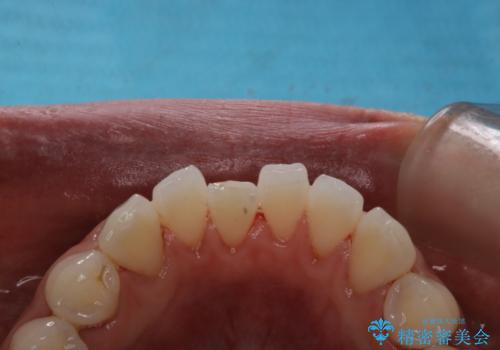

タバコによるヤニ、着色、歯の汚れをPMTC(60分コース)で除去。